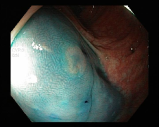

4.1.7 Gastrointestinal endoscopy

Endoscopies are used to detect diseases in the human digestive system. Images from inside the gastrointestinal tract can help physicians detect diseases early. The used dataset 777https://www.kaggle.com/datasets/abdallahwagih/kvasir-dataset-for-classification-and-segmentation contains eight image categories of the digestive system obtained through the endoscopy imaging technique, as shown in Fig. 8. There are a total of images that can be used in training and testing ML algorithms.